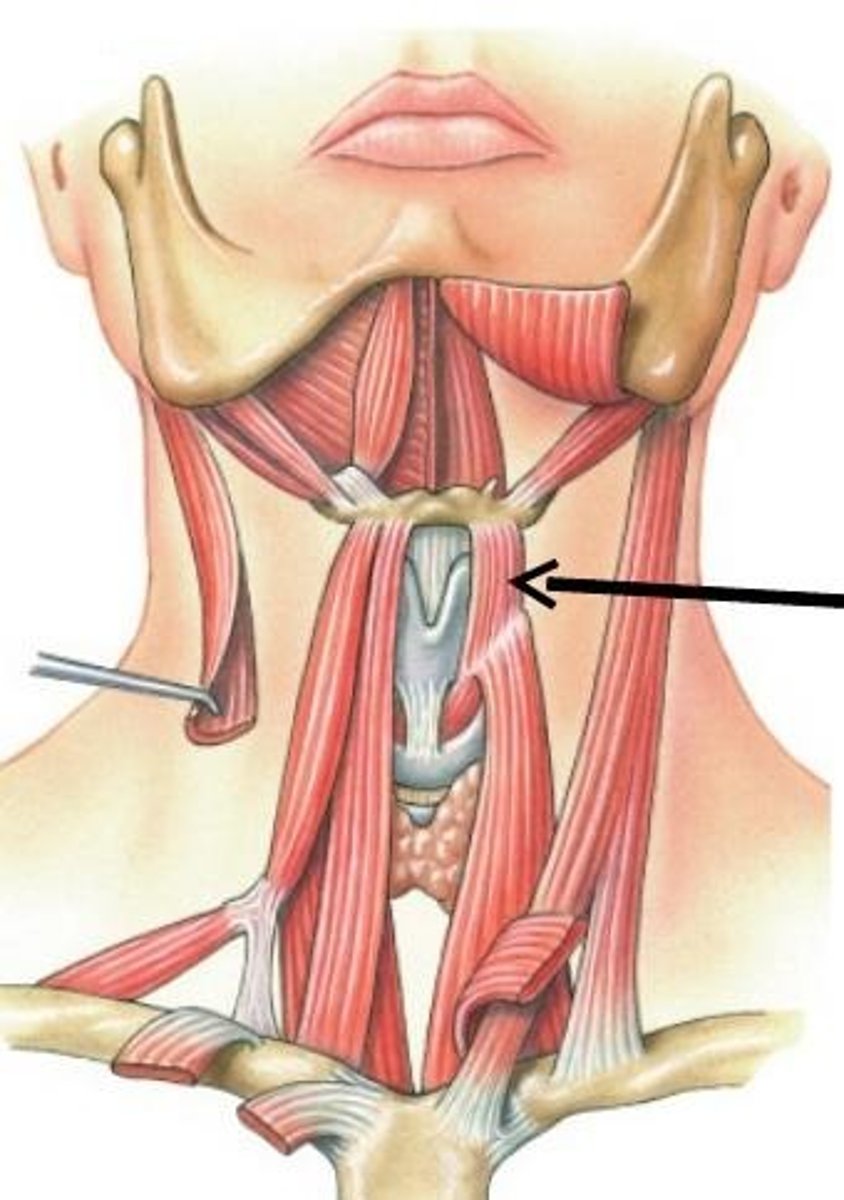

Stylohyoid m.

Origin: Styloid process

Insertion: Hyoid

Action: Elevate, retract

Digastric (two bellies)

Origin: Temporal/Mandible

Insertion: Hyoid

Action: Elevate

Mylohyoid m.

Origin: Mandible

Insertion: Hyoid

Action: Elevate

Geniohyoid m.

Origin: Mandible

Insertion: Hyoid

Action: Protract

Sternohyoid m.

Origin: Clavicle/sternum

Insertion: Hyoid

Action: Depress

Omohyoid (two bellies) m.

Origin: Clavicle/scapula

Insertion: Hyoid

Action: Depress

Thyrohyoid m.

Origin: Thyroid cartilage

Insertion: Hyoid

Action: Depress, Elevate larynx

Sternothyroid m.

Origin: Sternum

Insertion: Thyroid Cartilage Action: Depress

Hyoglossus m.

Origin: Hyoid

Insertion: Tongue (Lateral) Action: Depress, Pull inferior

Genioglossus m.

Origin: Mandible

Insertion: Tongue (Inferior) Action: Protrude, Pull inferior

Styloglossus m.

Origin: Styloid process

Insertion: Tongue

Action: Pull superior